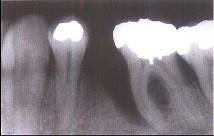

问题 牙槽骨垂直型吸收的特点,除外 ( )

选项 A.牙槽骨不发生水平方向的吸收 B.牙槽嵴高度降低不多,而牙根周围的骨吸收较多 C.垂直吸收多形成骨下袋 D.牙槽骨发生垂直或斜型方向的吸收 E.与牙根面形成角型的骨缺损

答案 A